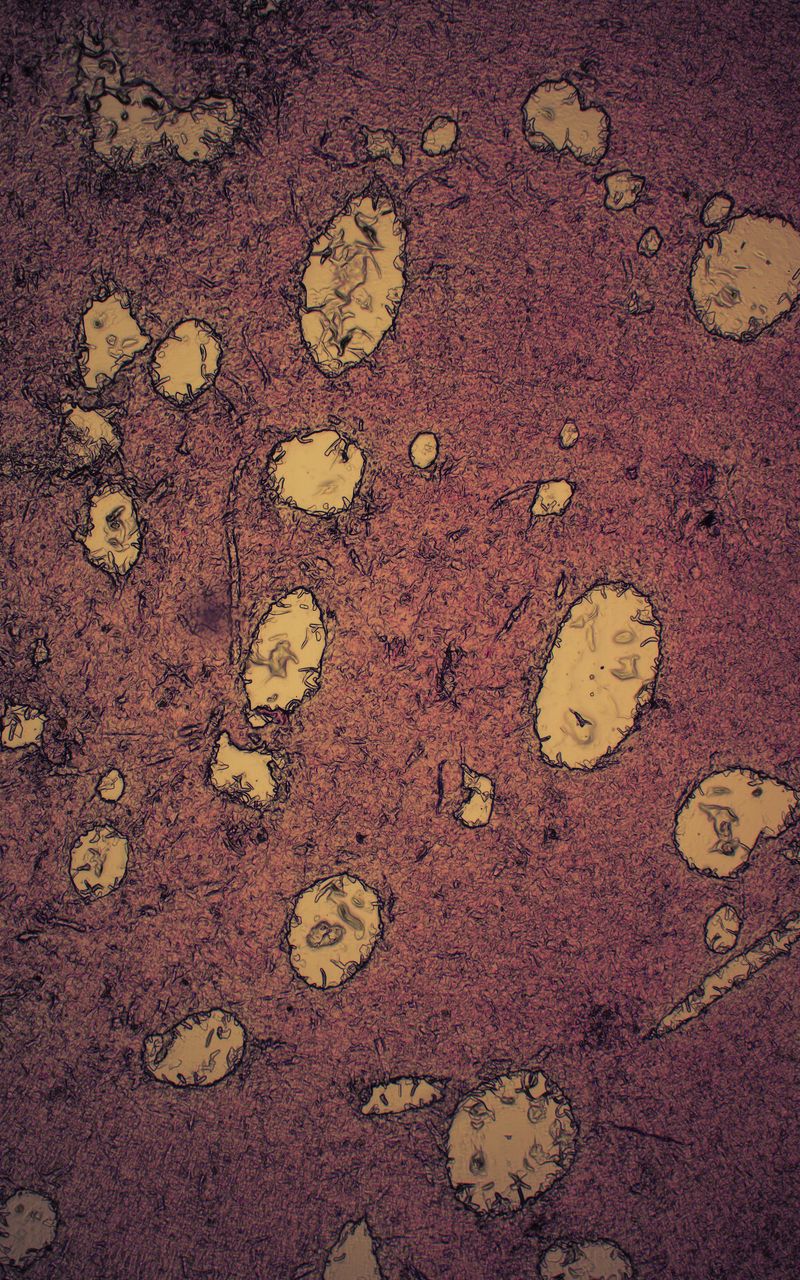

My work asks questions and challenges contemporary social and cultural attitudes towards the perception of death, the quality of life, reflections on the essence of humanity on philosophical and technological grounds. The story of our corporeality aims to begin a discourse about what has been tabooed or is socially marginalized:

medical bioengineering, technology in medical service, change in the perception of a dead body and the aspect of loss. Such a discourse could reveal the needs and solutions for the development of bioengineering in Poland. The increasingly appearing idea of transhumanism in this aspect considers dysfunctional elements of the human condition, such as disability, suffering, disease and ageing, to be undesirable, often still remaining only an idea but also a goal.